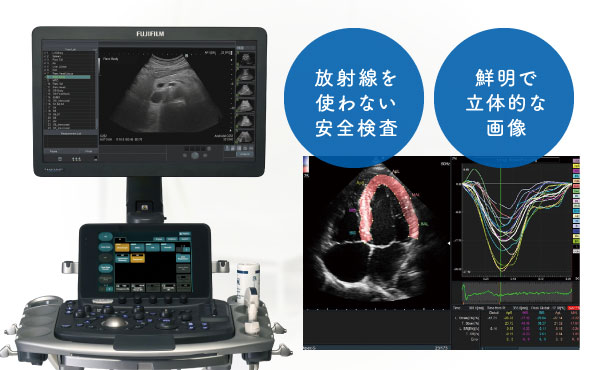

被ばくのない安心の検査機器

エコー(超音波検査機器)

超音波検査は体に負担をかけることなく内部の状態を詳しく調べられるのが大きな特徴です。放射線を使わないため被ばくの心配がなく、痛みもないため、小さなお子さまからご高齢の方まで安心して検査を受けていただけて、繰り返し検査による経過観察が可能です。

また先進の画像処理技術により、これまで以上に鮮明で立体的な画像を映し出せるため、病気の早期発見やより精密な診断につながります。